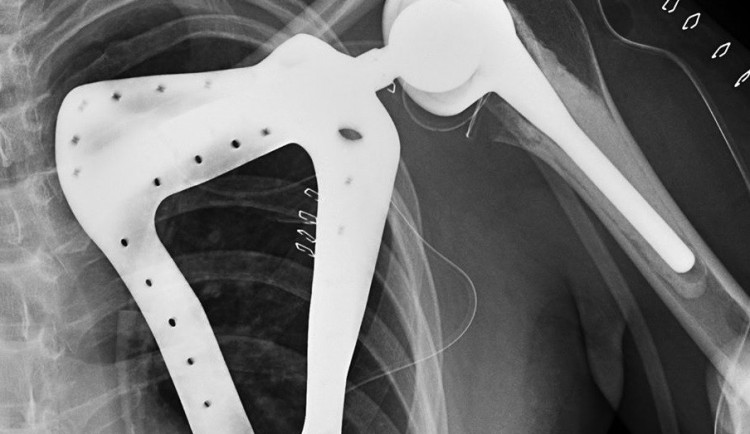

Paceintem svatoananeských lékařů byl teprve třiadvacetiletý mladík, jemuž před rokem odstranili celou lopatku pro nádor. Šlo se o levou končetinu s těžkým funkčním omezením a těžkým kosmetickým defektem. Mladík měl de facto nepoužitelné rameno - jeho pohyblivost byla nulová, protože hlavice pažní kosti se neměla o co opřít. Vzhledem k mladému věku pacienta se tak lékaři rozhodli jít do rozsáhlé implantace ramenního kloubu včetně lopatky.

„Operace trvala 3 hodiny, jednalo se o složitou operaci, navíc v ČR jedinečnou. Bylo nutné vypreparovat zádový sval a jím překrýt umělou lopatku,“ sdělil Tomáš Tomáš. „Náhrada lopatky byla pro pacienta vyrobena na míru, je z titanu a postříbřená z důvodu minimalizace infekce. Je vyrobena pomocí 3D tisku," doplnil.